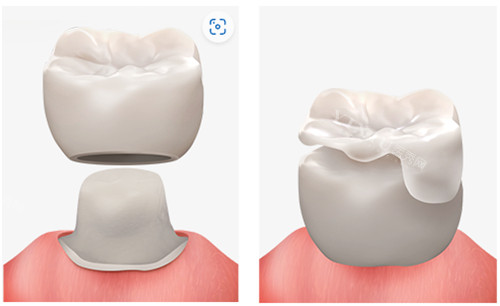

嵌体补牙:树脂嵌体1000-1500元/颗,陶瓷嵌体1500-3200元/颗。针对大面积缺损或牙体脆弱患者,嵌体修复可改善牙齿形态与功能,延长使用寿命。